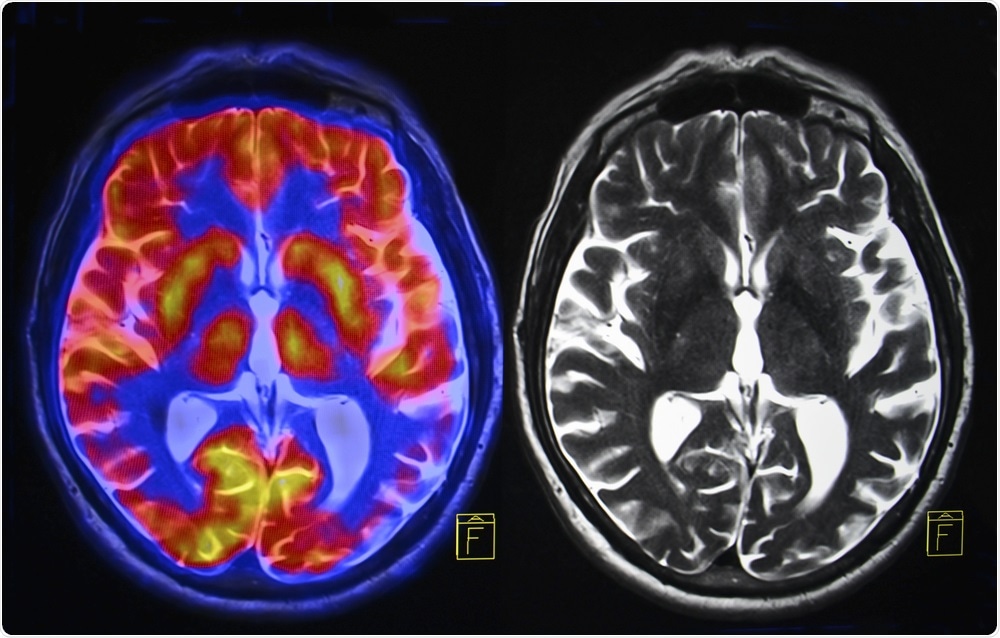

Physicians have defined a new form of dementia that may be more common than Alzheimer’s disease.Semnic | Shutterstock